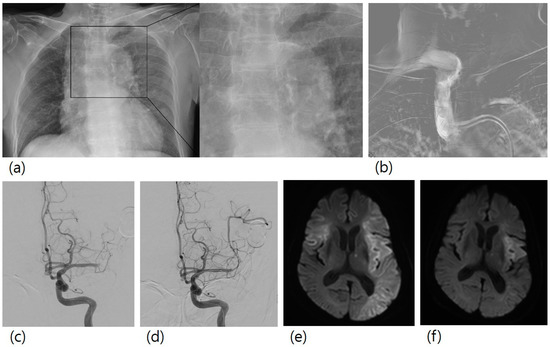

Association of Aortic Arch Calcification on Chest X-ray with Procedural Thromboembolism after Mechanical Thrombectomy for Acute Ischemic Stroke